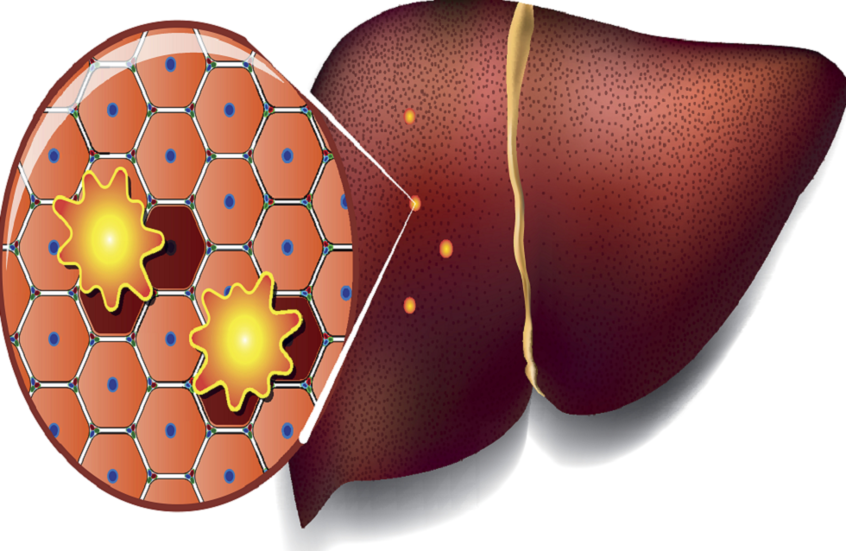

النظام الغذائي الغني بالدهون قد يهيئ الكبد للإصابة بالسرطان

كشف فريق من العلماء أن الدهون غير الصحية الشائعة في الأطعمة المصنعة تعرّض خلايا الكبد لإجهاد مزمن.

وهذا الإجهاد يجبر الكبد على الدخول في حالة "البقاء"، حيث يتوقف عن أداء وظائفه الطبيعية مثل تنقية الدم ومعالجة العناصر الغذائية وإزالة السموم، ويكتفي بمواجهة الضغط الناتج عن النظام الغذائي السيئ. ومع مرور الوقت، تتراجع خلايا الكبد إلى حالة بدائية تشبه الخلايا الجنينية، مستعدة للنمو السريع، لكنها تفقد القدرة على أداء وظائفها الحيوية بشكل كامل.

وأظهرت دراسة أجراها علماء من معهد ماساتشوستس للتكنولوجيا وجامعة هارفارد على الفئران، أن هذا الإجهاد الغذائي يؤدي إلى إعادة برمجة بطيئة لخلايا الكبد على مدى 15 شهرا. وبعد ستة أشهر فقط، بدأت خلايا الكبد المجهدة في الاستعداد للإصابة بالسرطان، حيث فُتحت مناطق من الحمض النووي تتحكم في نمو الخلايا، ما يضع التعليمات الجينية للسرطان في حالة تأهب قصوى، قبل سنوات من ظهور الورم.

وللتأكد من صحة النتائج لدى البشر، حلل العلماء عينات كبد من مرضى الكبد الدهني (MASLD) في مراحل مختلفة، بعضهم أصيب لاحقا بسرطان الخلايا الكبدية.

وأظهرت التحليلات علامات إعادة البرمجة الخلوية نفسها التي لوحظت في الفئران، وارتبطت قوة المؤشرات الجزيئية بارتفاع احتمالية الإصابة بالسرطان خلال 10–15 عاما.

ويعد سرطان الخلايا الكبدية أكثر أنواع سرطان الكبد شيوعا، ويصعب اكتشافه في مراحله المبكرة بسبب قلة الأعراض. وقد تشمل العلامات المبكرة فقدان الوزن غير المبرر وفقدان الشهية أو الشعور بالامتلاء بعد وجبة صغيرة. ومع تقدم المرض، قد تظهر أعراض مثل اليرقان والتعب والغثيان وسهولة النزف أو الكدمات وانتفاخ البطن نتيجة تراكم السوائل.

وتشير الدراسة إلى أن الإجهاد الغذائي الطويل الأمد قد يهيئ الكبد لتطور السرطان قبل ظهور أي أورام، مؤكدة أهمية الحد من استهلاك الدهون المشبعة والأطعمة المصنعة، ومتابعة صحة الكبد بانتظام، خاصة لدى الأفراد الذين لديهم عوامل خطر مثل مرض الكبد الدهني المزمن أو التهاب الكبد أو تليف الكبد.

نشرت الدراسة في مجلة Cell.

المصدر: ديلي ميل